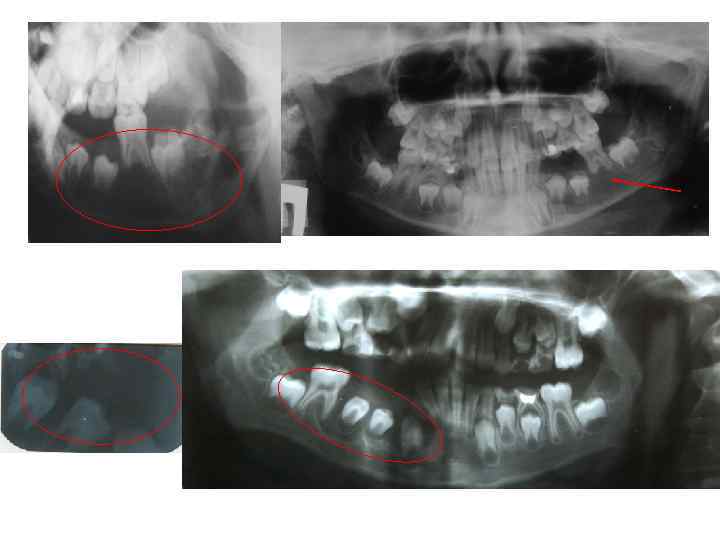

• Опухоль нижней челюсти справа. Смещение зубов тканями опухоли.

• 1. Рентгенологическое исследование. Исходные данные получают при обычной рентгенографии в нескольких проекциях. Она позволяет определить локализацию, форму, размеры опухолевого очага, степень деструкции костной ткани, наличие патологического перелома. При некоторых видах опухолей эффективна контрастная рентгенография.